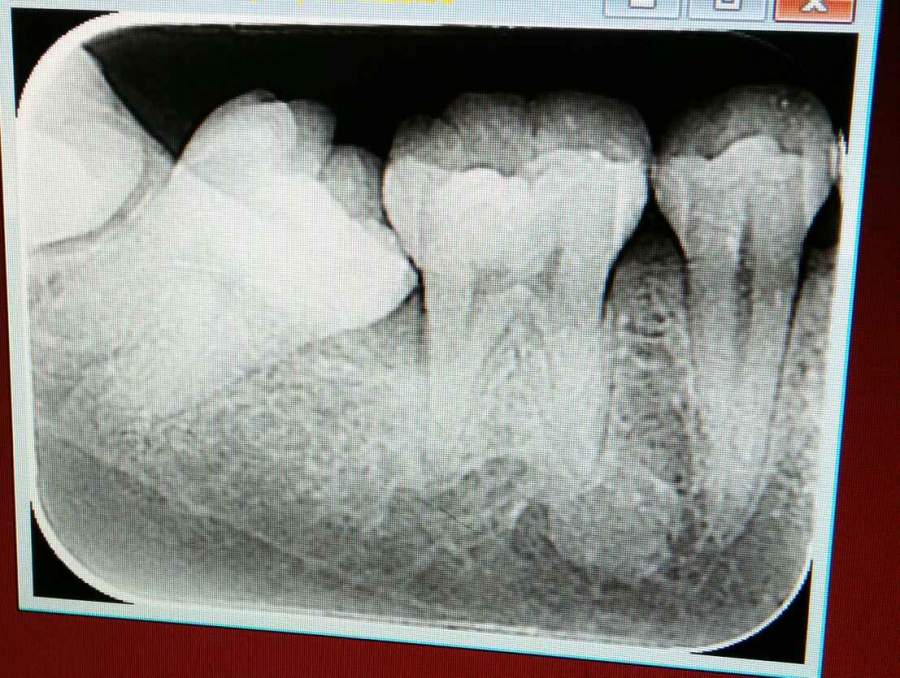

我的智齿还没长出来,第二磨牙和第一磨牙之间容易残留食物,这两天觉得牙疼,医生建议我拔掉两边的第二磨牙,不知各位大神有没有好的建议,是必须拔掉吗?拔掉的话上面最后的两颗牙是不是也需要拔掉,因为可以看到是蛀牙,虽然还没有洞洞,吃饭也用不到? @carci @wangyc3 发自小木虫Android客户端 |

你今年多大了。第二磨牙近中倾斜也是后面的智齿顶的。我觉得你最好还是把最后智齿拔掉。然后通过在后面种植支抗的钉的方式把第二磨牙矫正。这样最好。但就是做正畸也不便宜。 发自小木虫Android客户端 |